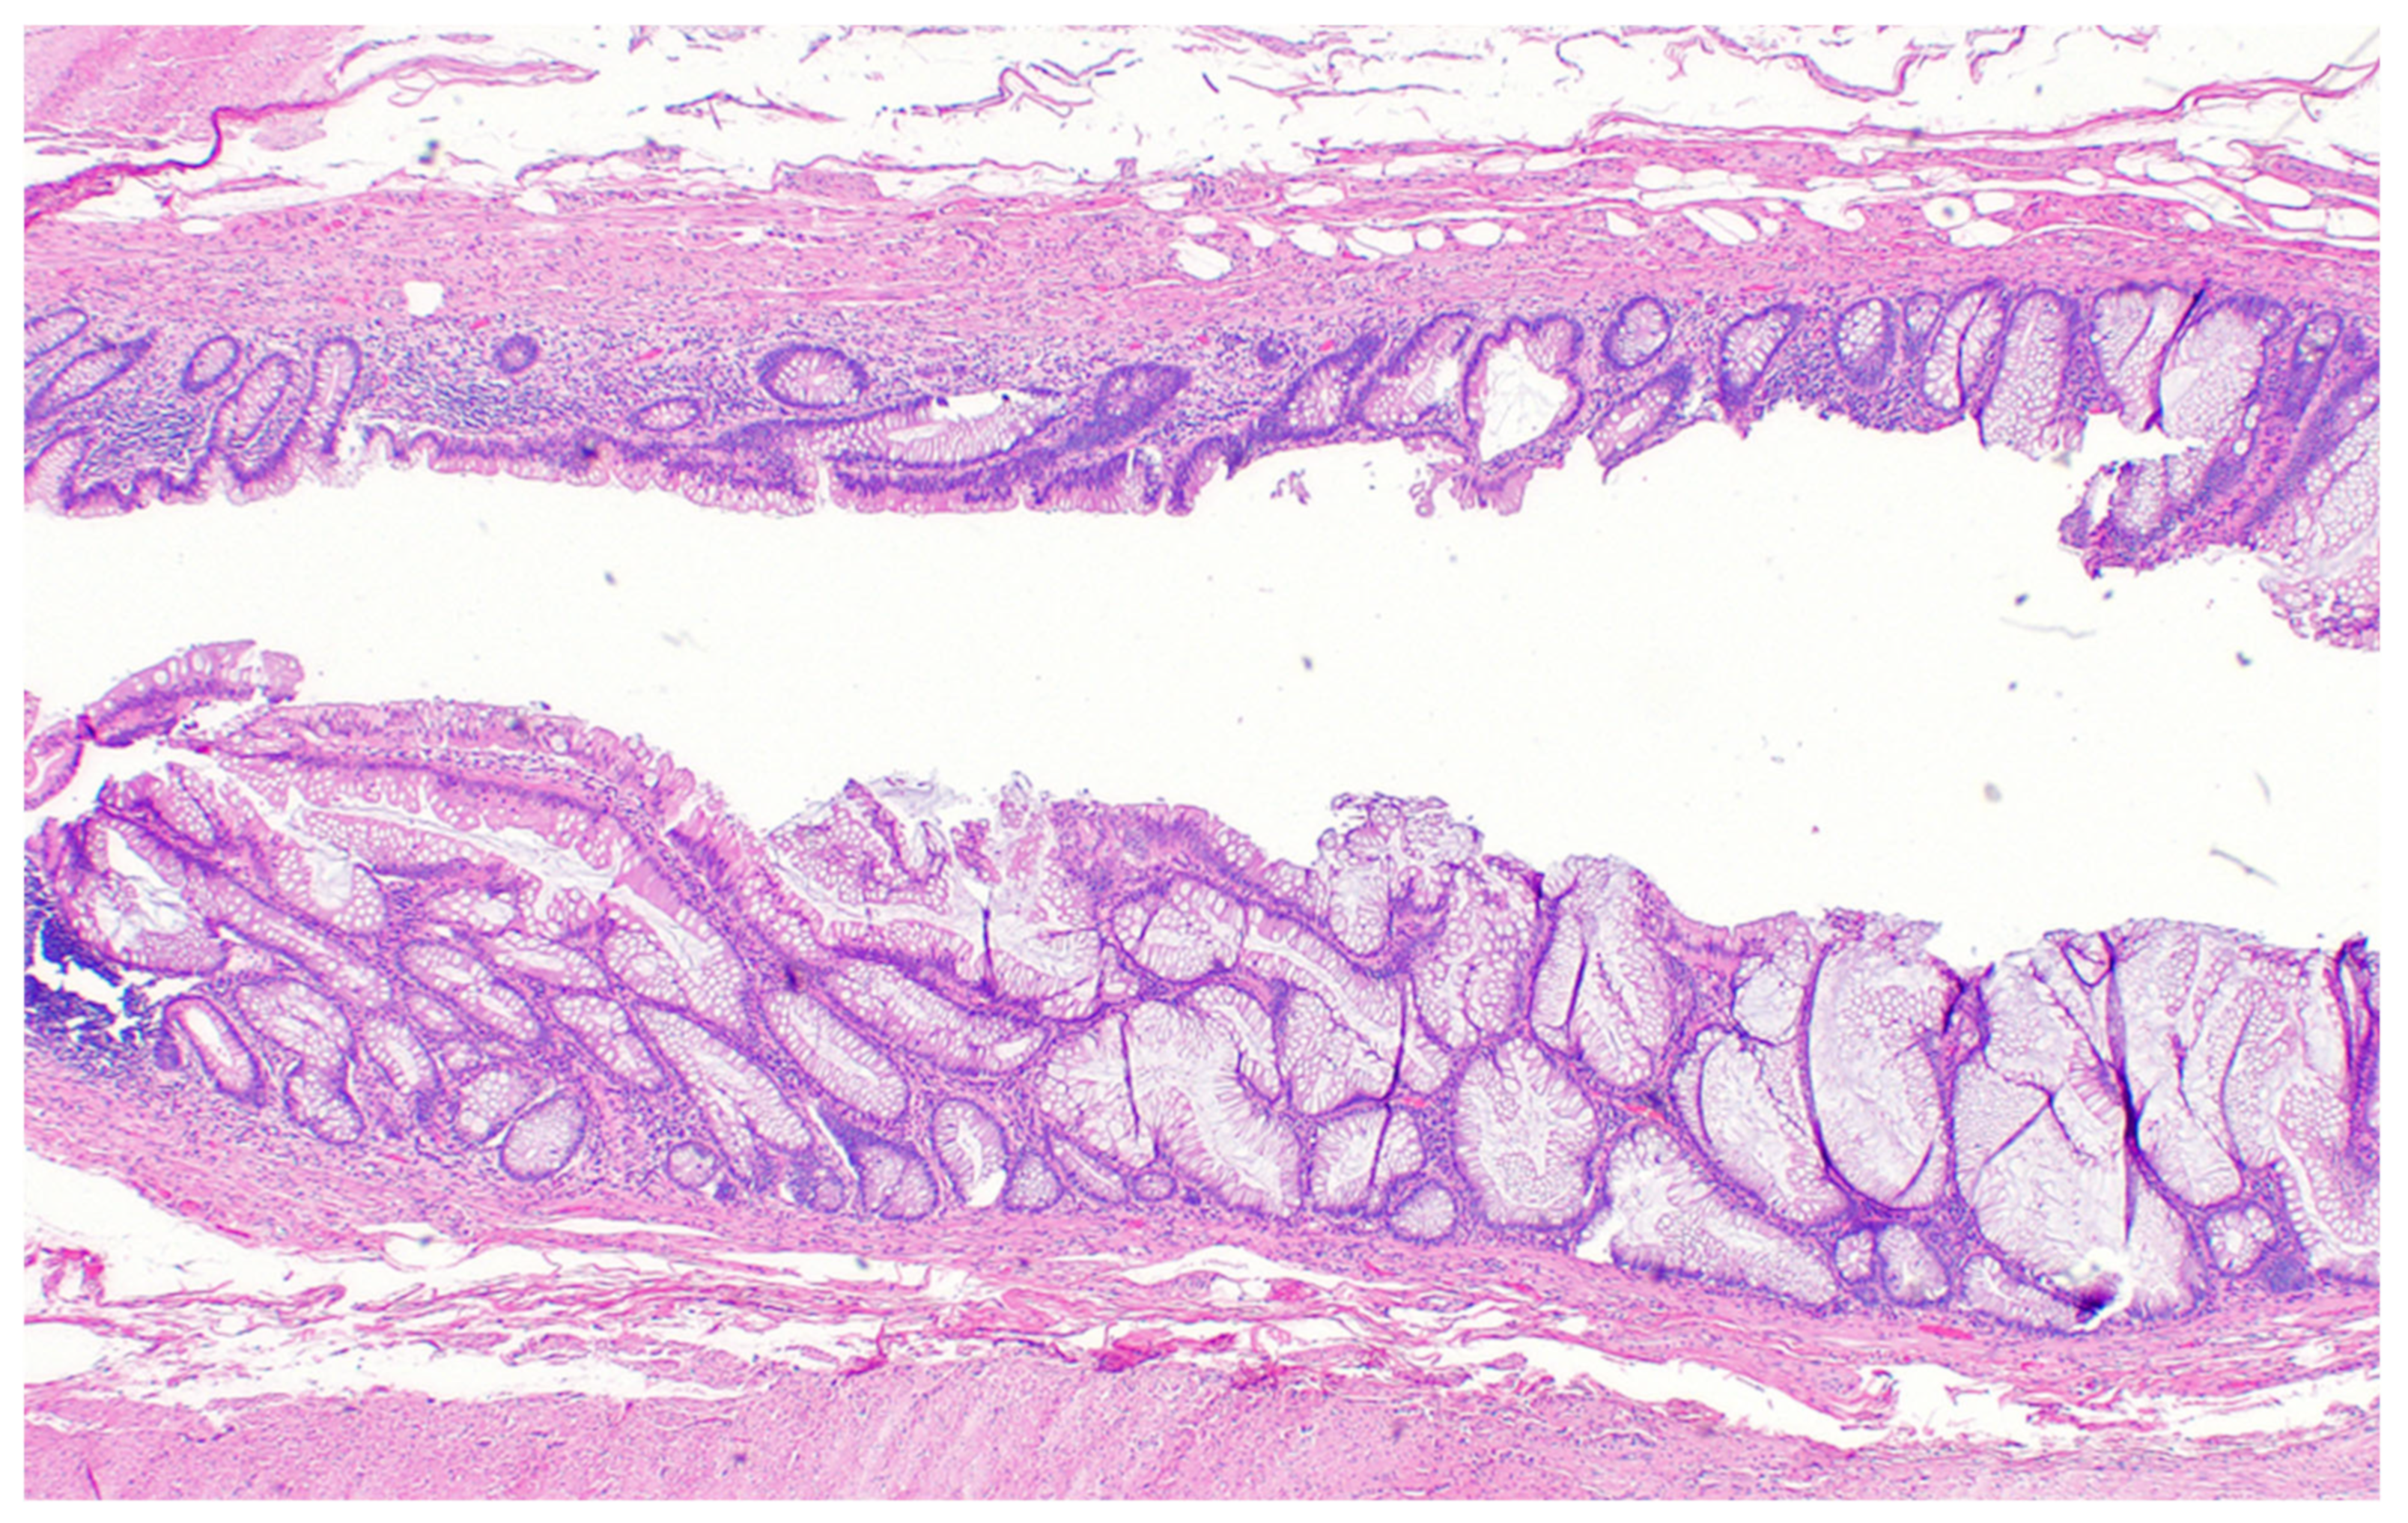

Figure 8. Pathological specimen (40×). The wall of the appendix is intact, there is no sign of perforation and no signs of malignancy, and mucin is only in the appendicle lumen.